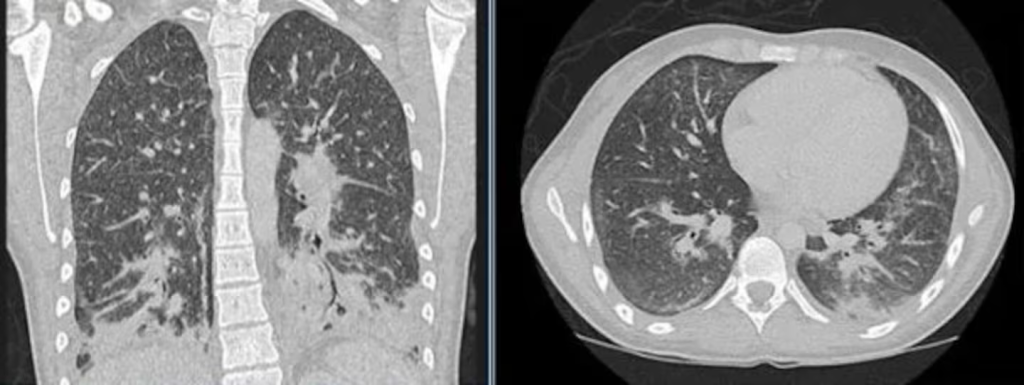

Una joven de Inglaterra tuvo que ser hospitalizada de urgencia tras una semana de intensa tos, escalofríos, fiebre alta y dificultad respiratoria. Al principio, los médicos creyeron que se trataba de neumonía bacteriana, pero al realizarle unas tomografías descubrieron que sus pulmones estaban llenos de “opacidades en vidrio esmerilado”, producto de haber usado el vaper de su novio durante un mes.

Normalmente, los pulmones sanos se ven negros en las radiografías y las tomografías computarizadas, pero en estas, gran parte se veía gris, lo cual indica que los sacos de aire de los pulmones podrían estar llenos de líquido u otras sustancias.